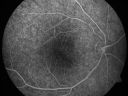

FLUORESCEIN ANGIOGRAPHY: The FA shows some irregular hyperfluorescence in the macula, which is mostly of a transmission than a blockage suggesting that there is some loss of pigmentation of the retinal pigment epithelium.